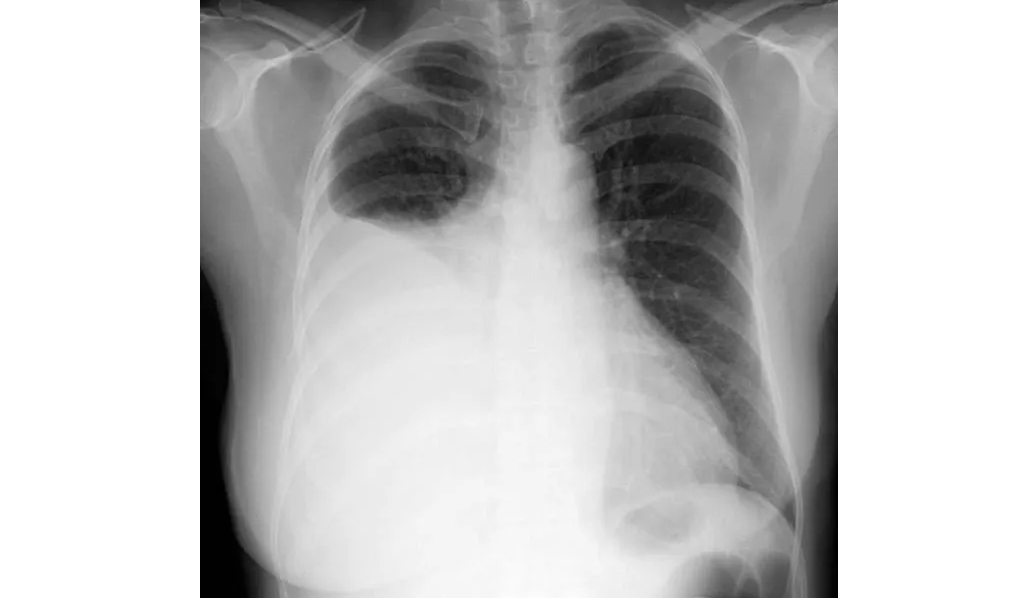

Neumonía adquirida en la comunidad: una revisión

La neumonía adquirida en la comunidad es común y puede provocar sepsis, síndrome de dificultad respiratoria aguda o muerte. El tratamiento de primera línea varía según la gravedad y la etiología de la enfermedad. Los pacientes hospitalizados con sospecha de NAC bacteriana y sin factores de riesgo de bacterias resistentes pueden ser tratados con una terapia combinada de β-lactámicos/macrólidos, como ceftriaxona combinada con azitromicina, durante un mínimo de 3 días. JAMA, 16 de septiembre de 2024.